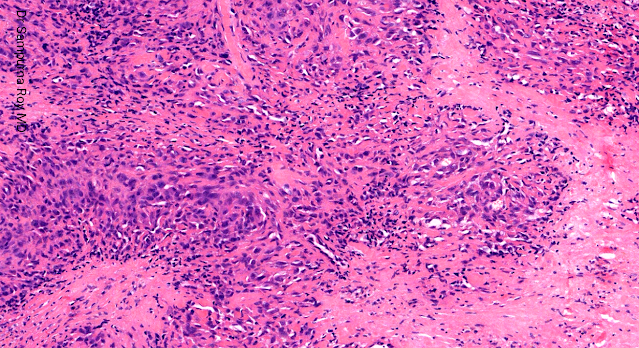

Immunohistochemical staining shows that the cells are positive for both mesenchymal markers smooth muscle actin and CD34 and epithelial markers cytokeratin and epithelial membrane antigen.